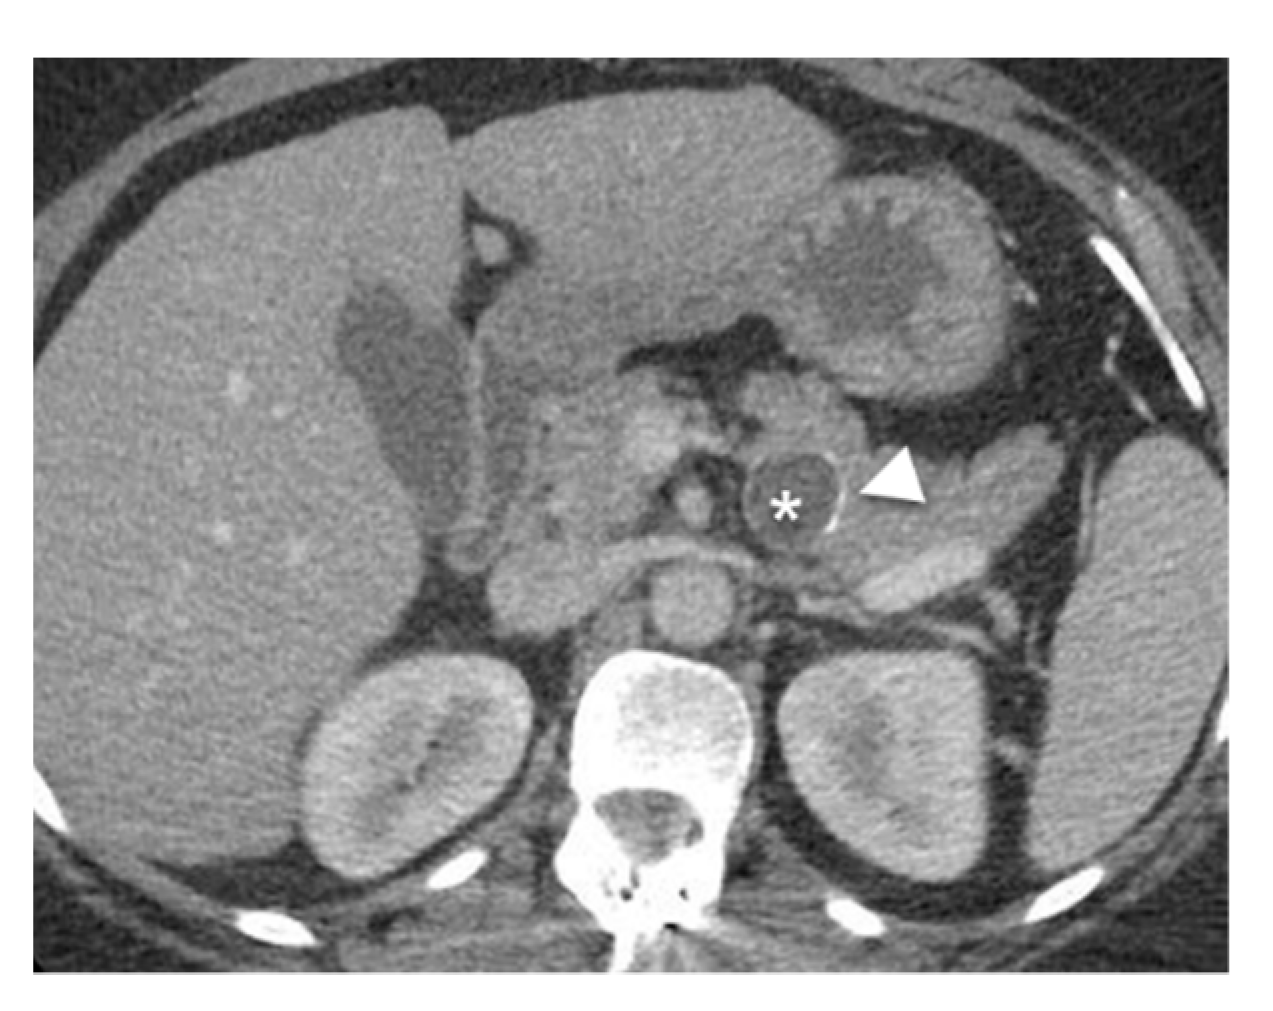

- Bordeianou, L.; Vagefi, P.A.; Sahani, D.; Deshpande, V.; Rakhlin, E.; Warshaw, A.L.; Fernandez-del Castillo, C. Cystic pancreatic endocrine neoplasms: A distinct tumor type? J. Am. Coll. Surg. 2008, 206, 1154–1158. [Google Scholar] [CrossRef]